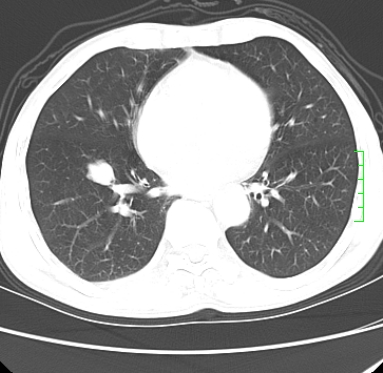

m,73y。膝关节疼痛伴双下肢水肿。入院常规胸片发现结节灶。增强为静脉期。

肿块周围可见局限性气肿,考虑肺癌可能性大。双肺上叶继发型肺结核。

指套征,强化明显,近侧肺组织局限性肺气肿,考虑支气管类癌,慢支、肺气肿、双上陈旧性tb、冠脉钙化。

鉴别:先天性支气管闭锁,变态反应性支气管肺曲霉菌病,肺癌,支气管囊肿,支扩黏液嵌塞。

1)考虑右肺下叶周围型肺癌。2)右肺上叶及左肺感染性病变(结核可能)。3)肺气肿。4)冠状动脉钙化。